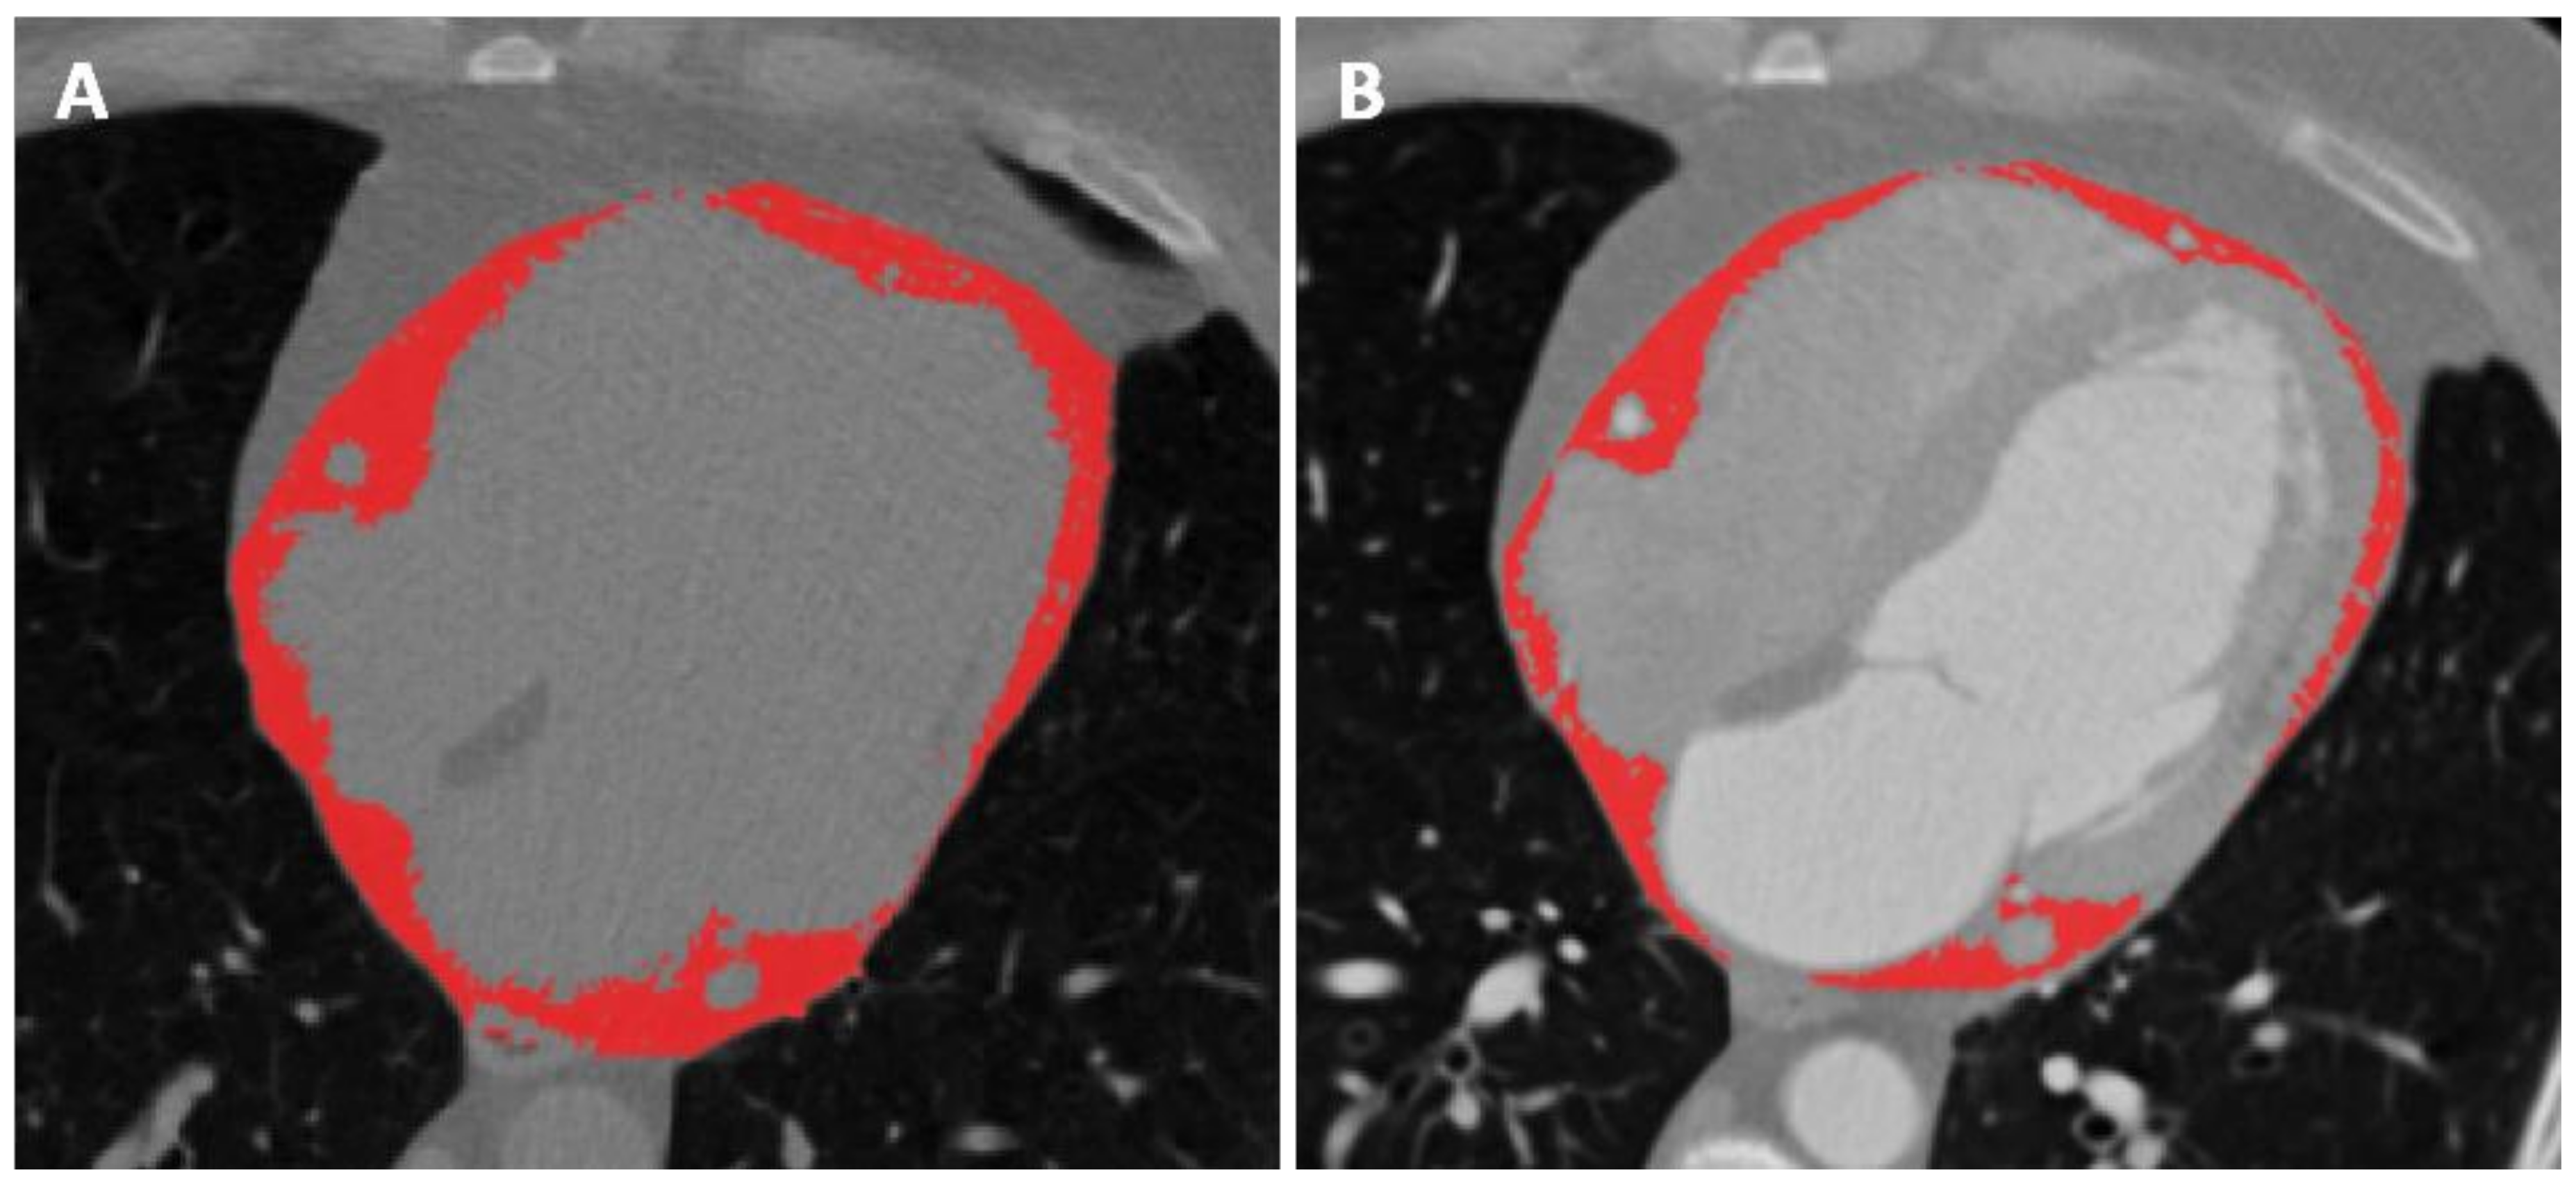

2.3. Image Analysis